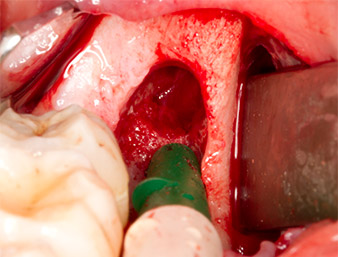

To expose the root remnant with as little trauma as possible to the tissue, a further instrument was used (Piezomed S2) that is primarily indicated for preparing the lateral window in augmentations of the sinus floor. The diamond-coated ball was additionally used to smooth sharp bone edges (Fig. 6 and 7). All the Piezomed attachments were used with the relevant automatic default setting without booster function.